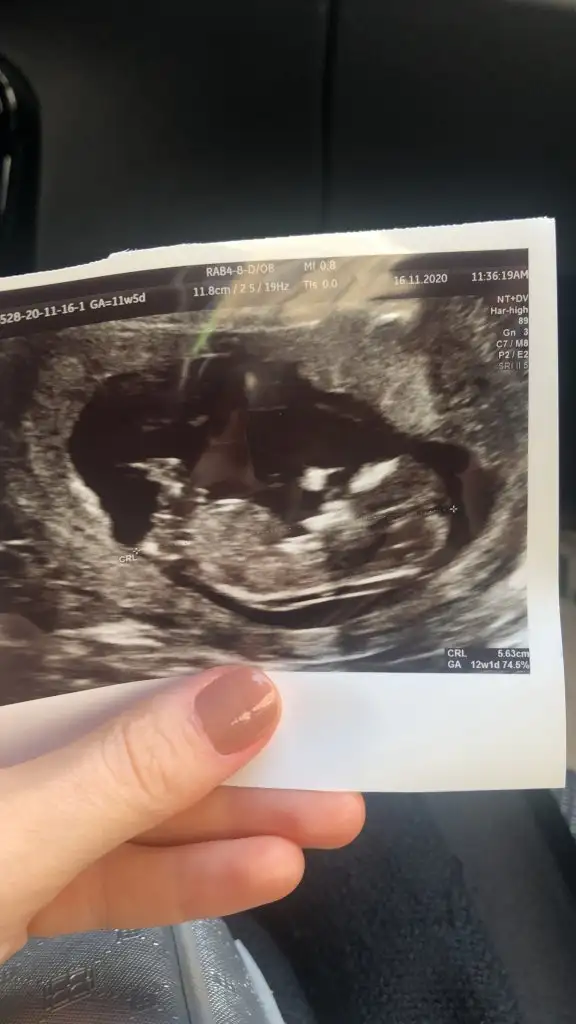

Evet erkek dik görünüyorLütfen bana da yorum yapar mısını?doktor erkek olabilir dedi 12+1 deki ve 12+4 deki ultrason resimleri

Elimdeki son usg bu, çok net değil ama belki siz görebilirsiniz.Sağlıkla gelsin yinede göstereyim çizdim usgnizi az önceben şok demekki pozisyon la alakalı değişim oluyor Eki Görüntüle 2726610

Hem net değil hem 14 den sonra organı oluşuyorElimdeki son usg bu, çok net değil ama belki siz görebilirsiniz.

Kaç haftalikta Dr kiz dedi tabiki sağlıkla gelsin minnosElimdeki son usg bu, çok net değil ama belki siz görebilirsiniz.